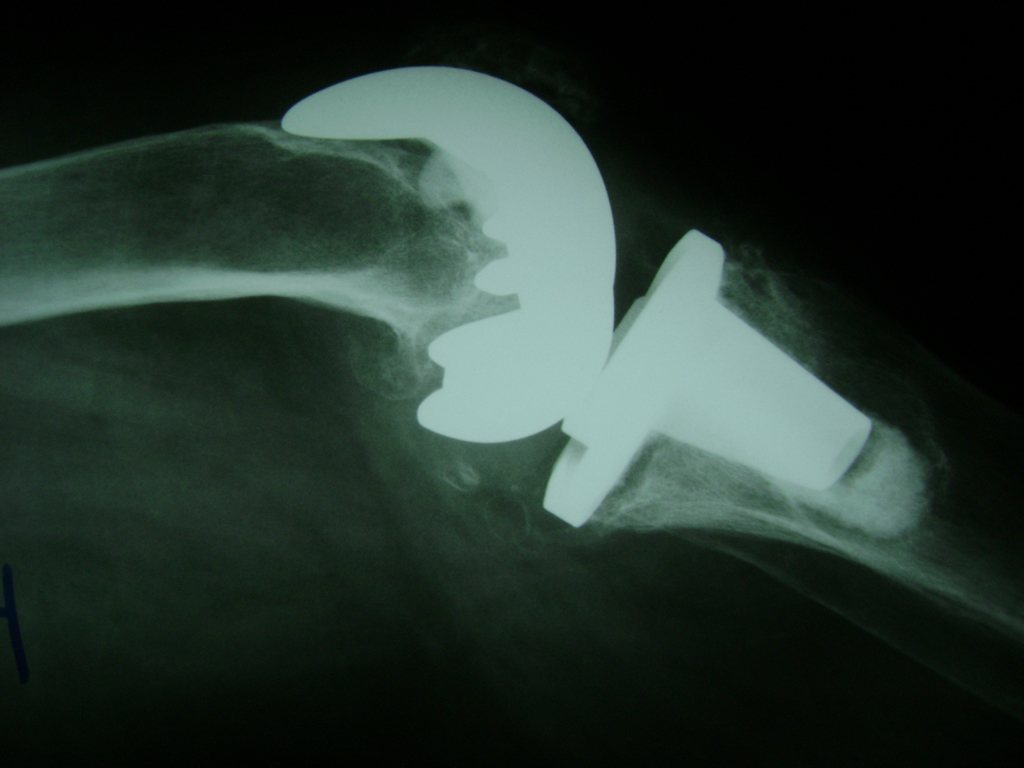

Cirugías de Cadera